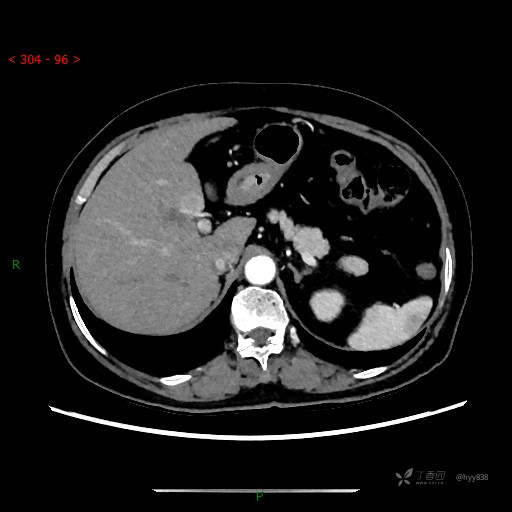

增强动脉期